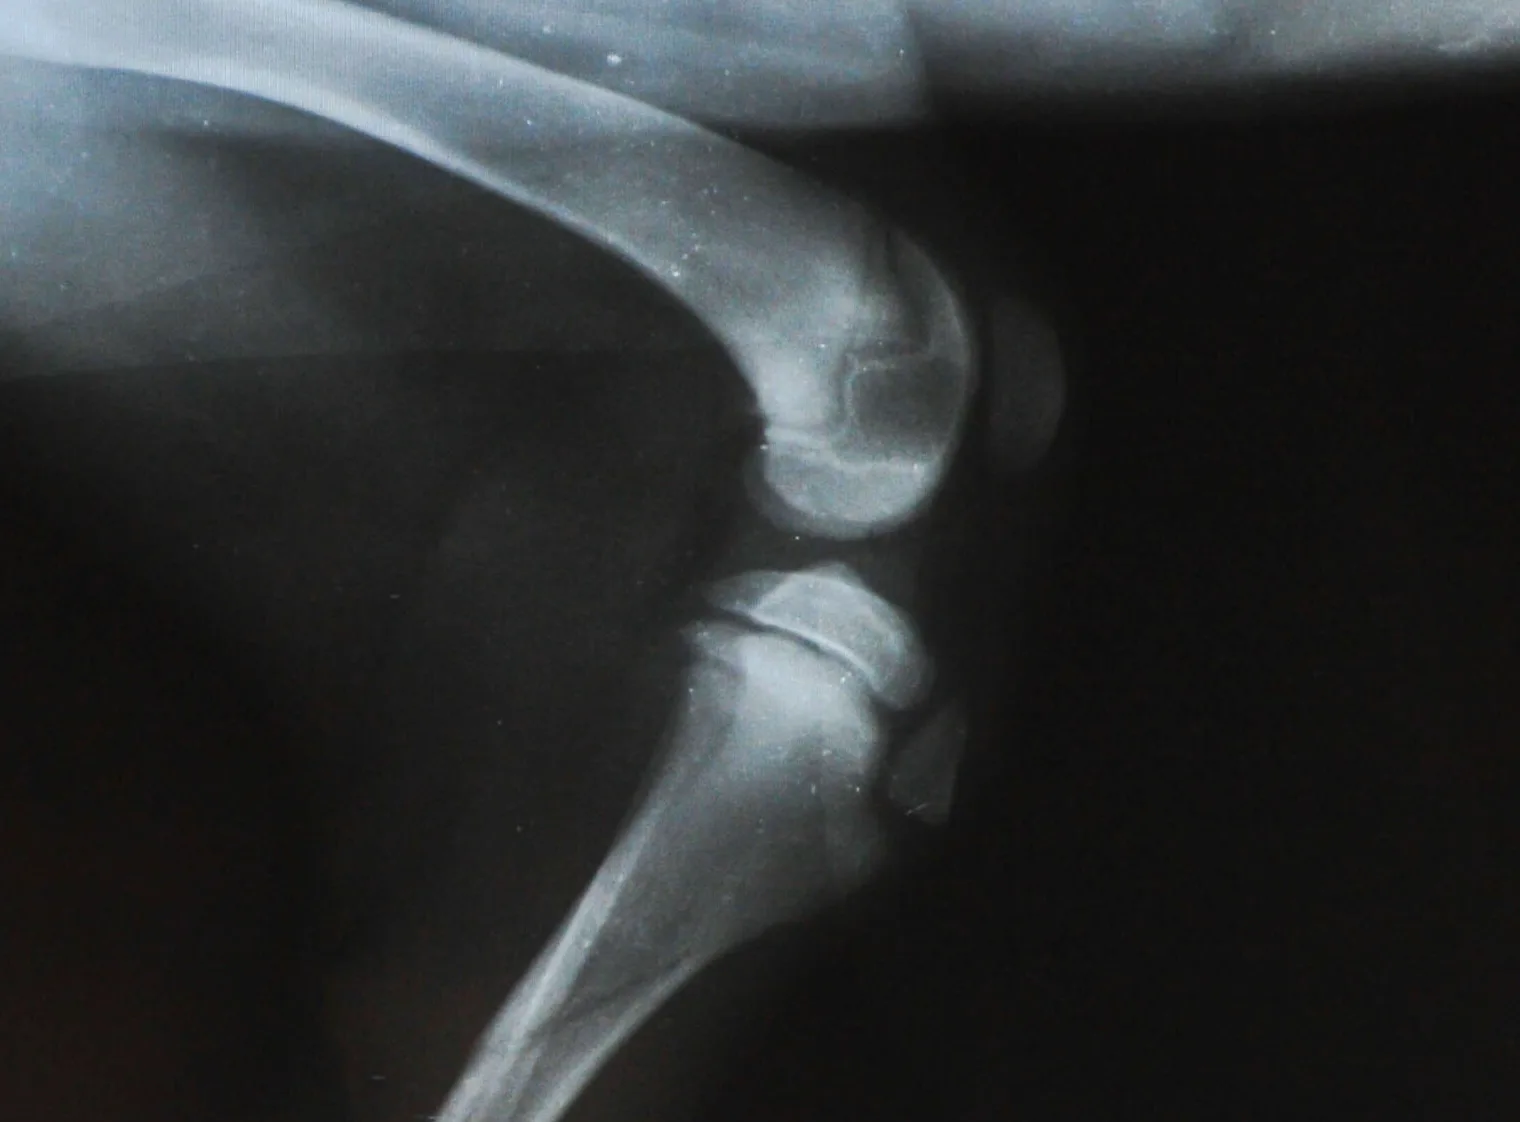

Osteoarthritis is a major issue for senior dogs

- Chondroitin sulphate and glucosamine: In the healthy state, glucosamine is made in the joint, but in osteoarthritis, this process is compromised, and so to offset this, glucosamine can be included in the diet. Glucosamine supplements are made from the exoskeletons of shrimp, lobsters and crabs. Chondroitin is also sourced from animal or fish cartilage and acts in the body to slow the rate of cartilage damage. Therefore, chondroitin and glucosamine work together to promote healthy cartilage in the joints. Most supplements have a combination of glucosamine and chondroitin sulphate and other compounds such as manganese ascorbate and flavonoids. They are very well researched, and there is good evidence for their benefit to joints.